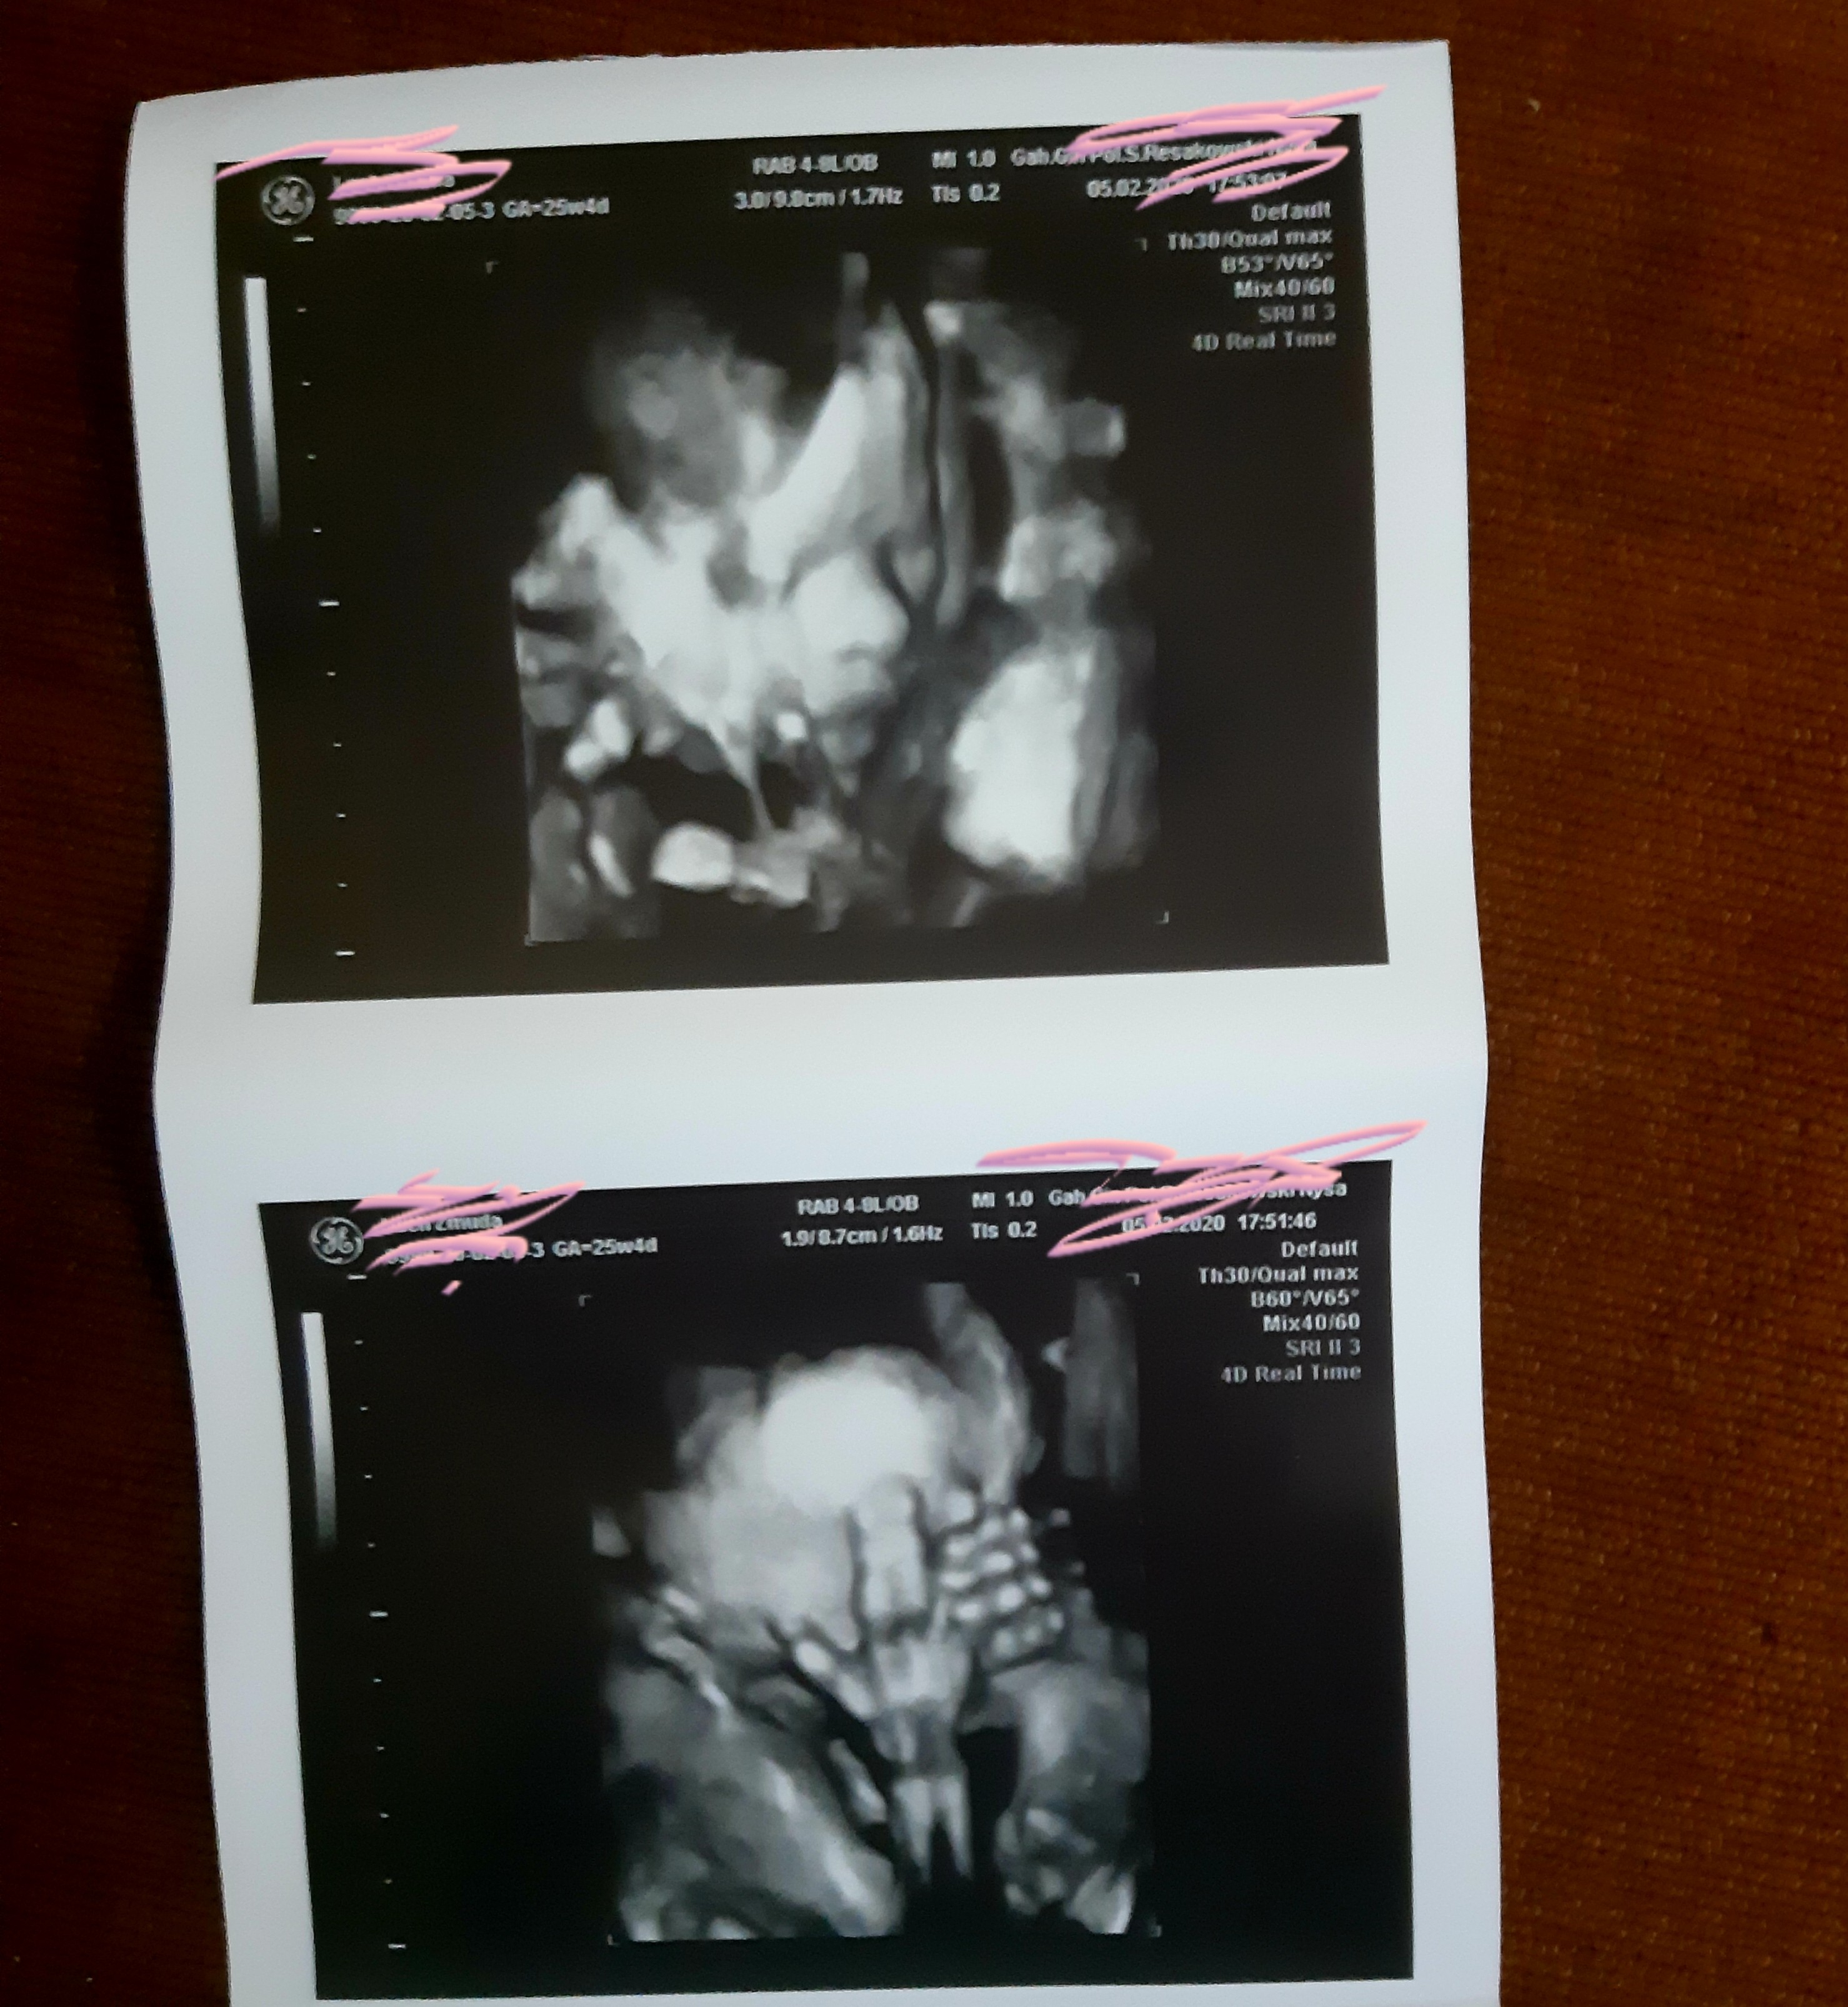

A tez 26 tc?To ja teź miałam w poniedziałek 27mm na IP jak pojechałam po twardnieniach brzucha i wczoraj mój lekarz założył mi pessar i mam nakaz leżenia w domu. Co lekarz to inna opinia![]()